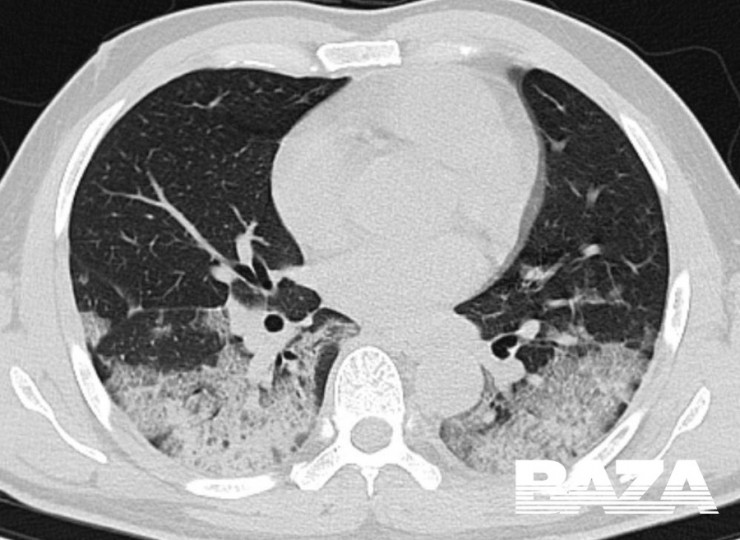

Одна из отличительных особенностей вирусной пневмонии - это симметричное поражение легких с полисегментарными воспалительными изменениями (в нескольких частях, то есть в разных долях и разных не смежных сегментах). Другие виды пневмонии развиваются, как правило, в пределах одной доли легкого, а не везде. Так, при заболевании COVID-19 на компьютерных томограммах видны уплотнения легочной ткани, похожие на прозрачные потертые пятна. В медицине такие патологии называют симптомом "матового стекла".

На пиковой стадии вирусной пневмонии (она развивается на 10–13-й день) появляются множественные уплотнения по типу "матового стекла" с различной протяженностью. Причем поражение может быть более обширным - субтотальным, с вовлечением всей доли целиком, а не только в пределах одного сегмента.